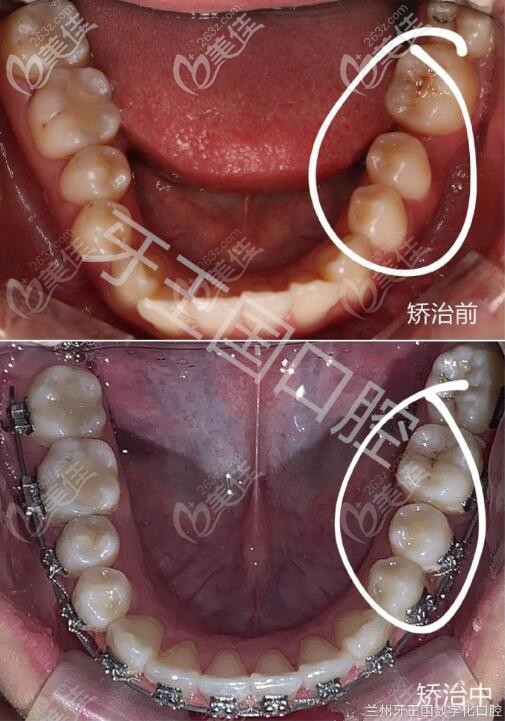

兰州牙王国口腔诊疗范围:牙齿矫正、种植牙、牙周炎、牙髓治疗、镶牙、牙齿美学修复儿童牙齿(窝沟封闭、涂氟等)。